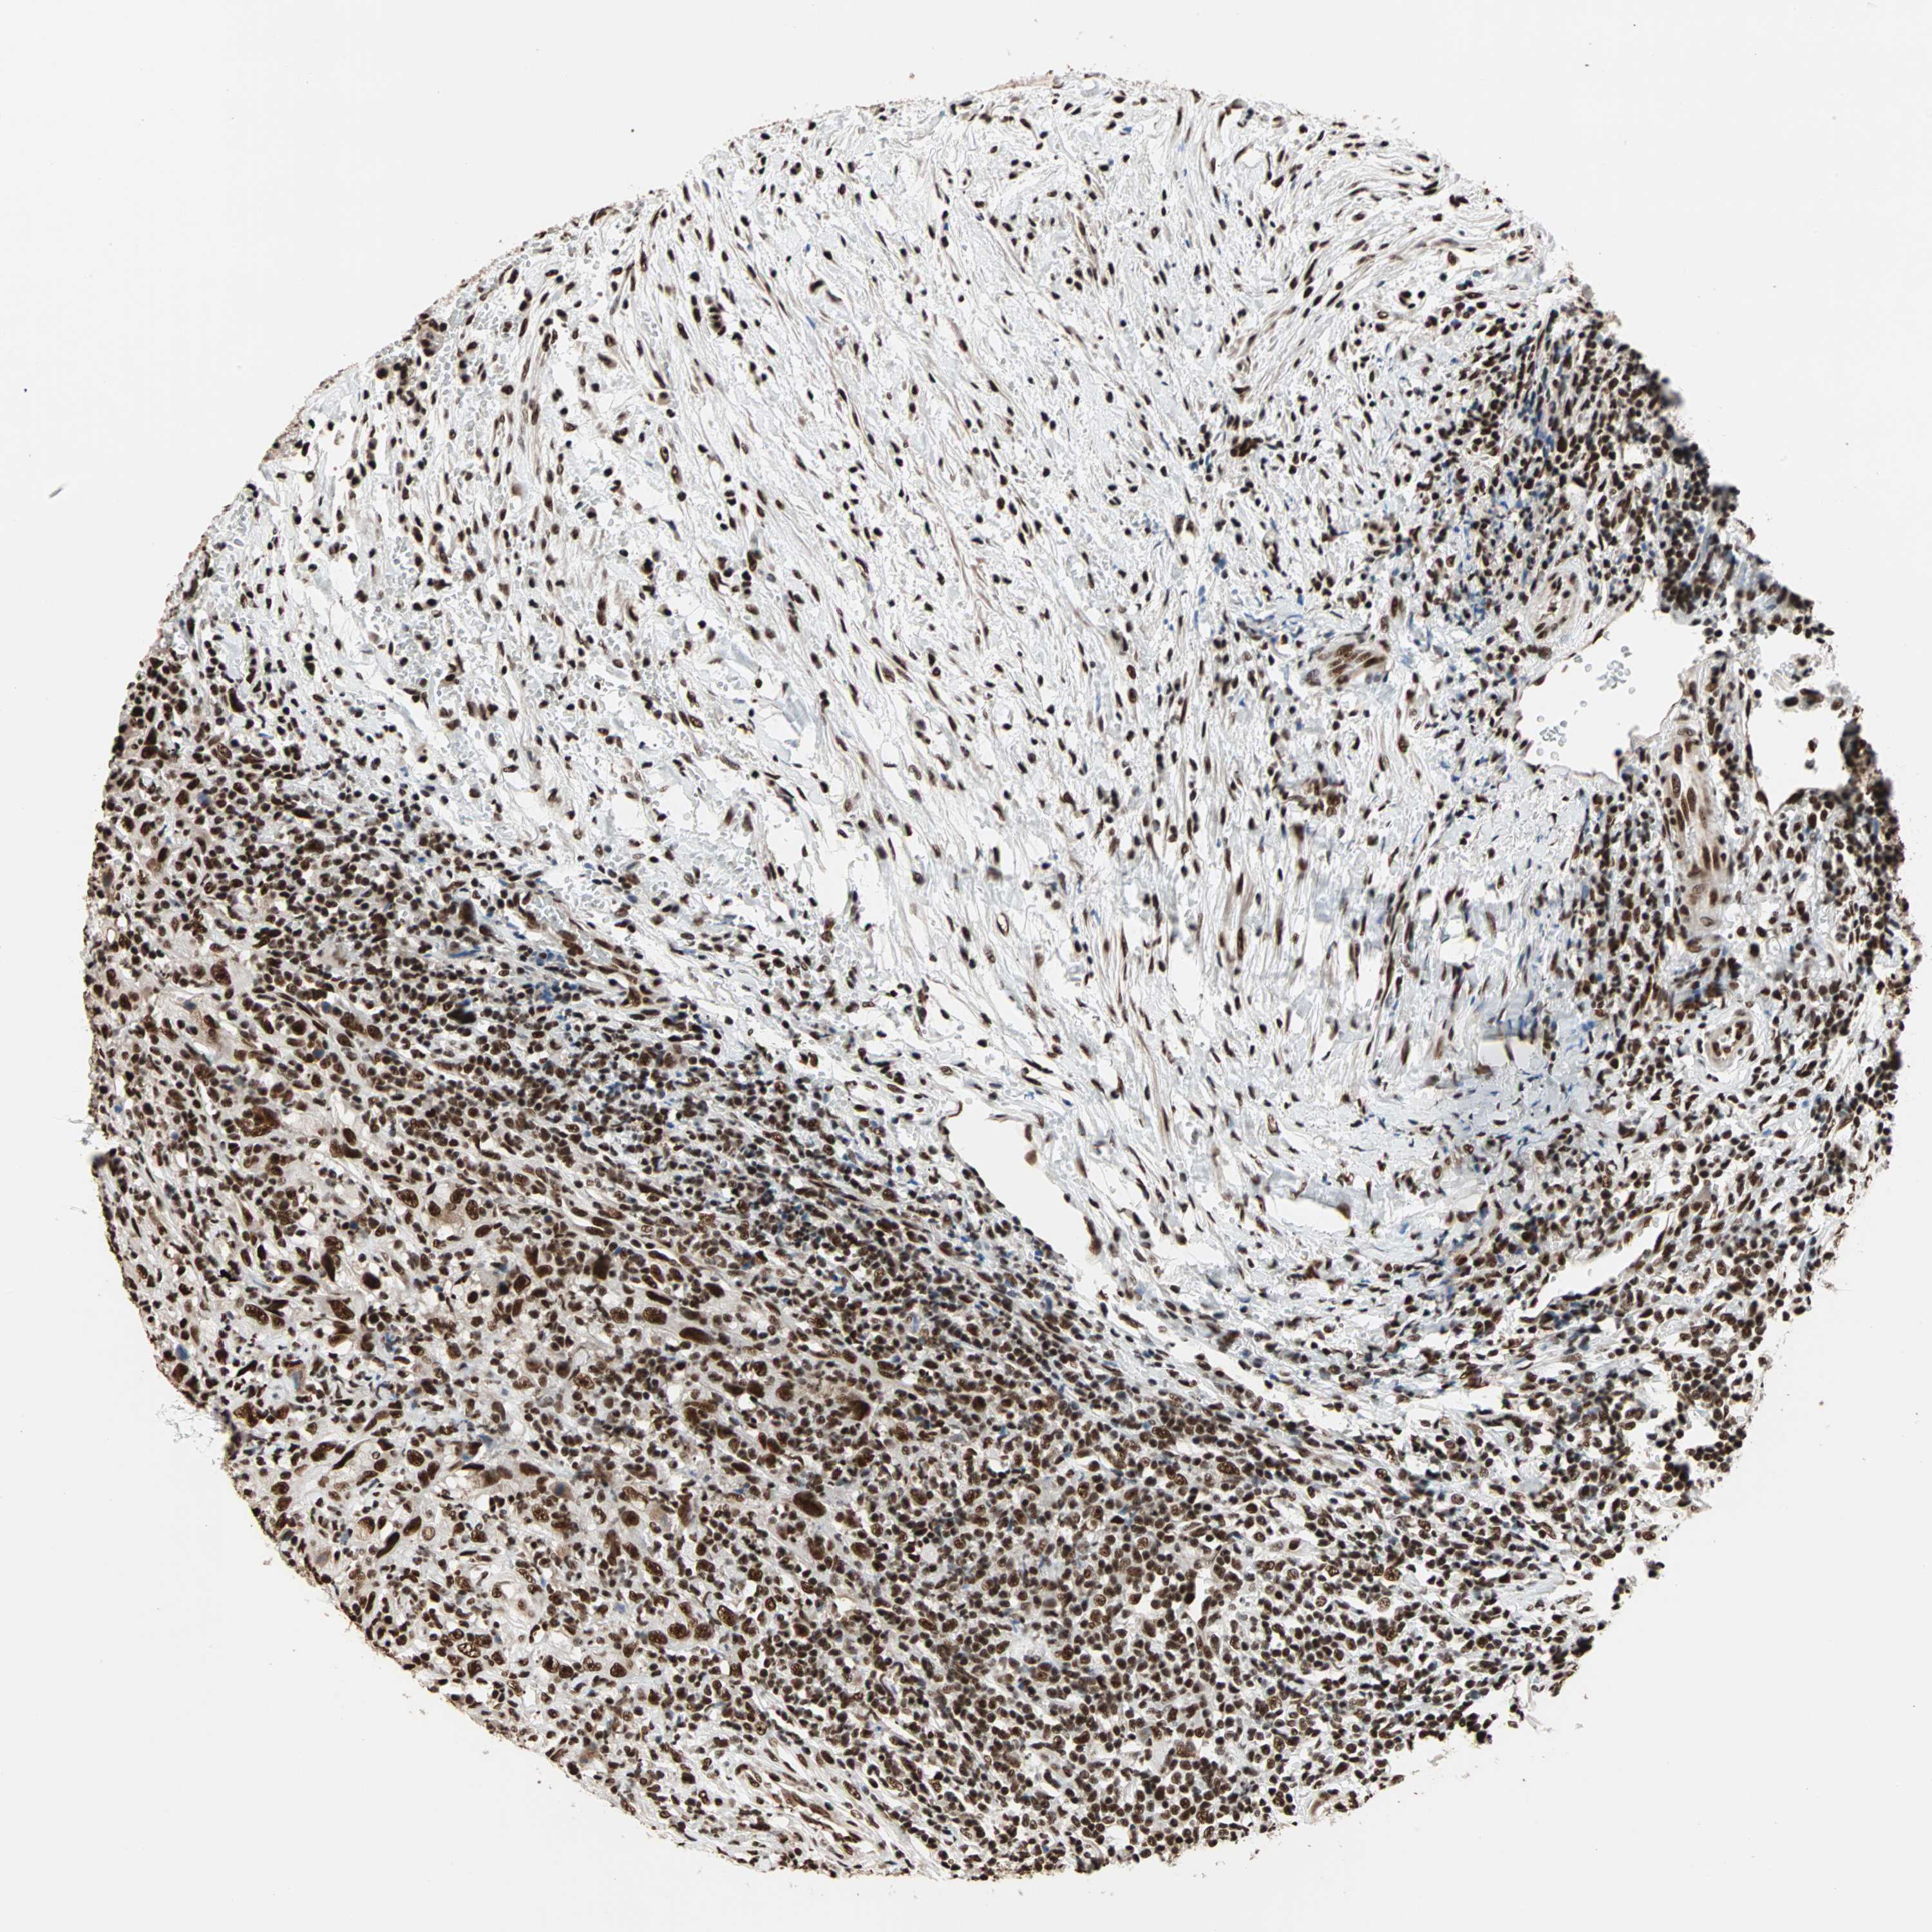

UROTHELIAL CANCER - Protein expressioni

A mouse-over function shows sample information and annotation data. Click on an image to view it in a full screen mode. Samples can be filtered based on level of antibody staining by selecting one or several of the following categories: high, medium, low and not detected. The assay and annotation is described here.

Note that samples used for immunohistochemistry by the Human Protein Atlas do not correspond to samples in the TCGA dataset.

Antibody stainingi

Antibody staining in the annotated cell types in the current human tissue is reported as not detected, low, medium, or high, based on conventional immunohistochemistry profiling in selected tissues. This score is based on the combination of the staining intensity and fraction of stained cells.

Each image is clickable and will lead to virtual microscopy that enables deeper exploration of all samples and also displays staining intensity scores, fraction scores and subcellular localization as well as patient and tissue information for each sample.

Antibody HPA007484

Staining

High

Medium

Low

Not detected

Intensity

Strong

Moderate

Weak

Negative

Quantity

>75%

75%-25%

<25%

None

Location

Nuclear

Cytoplasmic/membranous

Cytoplasmic/membranous,nuclear

Urothelial carcinoma, Low grade

Urothelial carcinoma, High grade